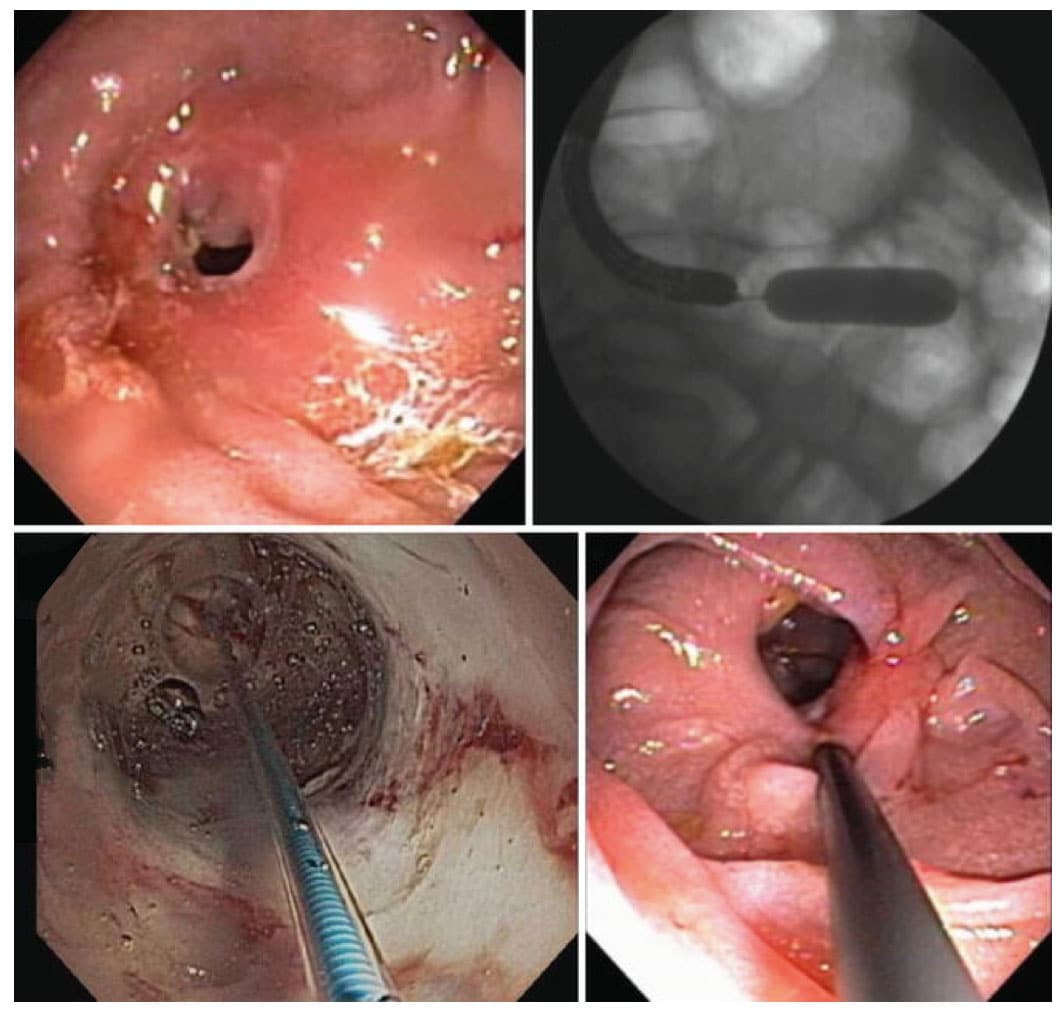

Καινοτομία στη θεραπεία του δακτυλίου Schatzki αποτελεί η θερμική διατομή με ηλεκτροδιαθερμία. Το ηλεκτρικό μαχαιρίδιο («Needle Knife Papillotom»), που χρησιμοποιείται για την ενδοσκοπική σφιγκτηροτομή, προωθείται μέσα από το κανάλι βιοψίας του ενδοσκοπίου μέχρι τη θέση του δακτυλίου. Με αυτό γίνονται επιμήκεις τομές του δακτυλίου σε ακτινωτή διάταξη, με τη διοχέτευση ηλεκτρικού ρεύματος. Η επιτυχία της μεθόδου ανέρχεται σε ποσοστό 82% των ασθενών, χωρίς ν’ αναφέρονται σοβαρές επιπλοκές.

Εφόσον στην ακτινολογική απεικόνιση η στένωση προσλαμβάνει εικόνα διαφράγματος, επιχειρείται πριν από τη διαστολή η ενδοσκοπική διατομή του ουλώδους δακτυλίου με το ηλεκτρικό μαχαιρίδιο βελόνης («Needle Knife Papillotom») σε ακτινωτή διάταξη, τουλάχιστον σε τέσσερα σημεία. Τα ξένα σώματα που ανευρίσκονται στην αναστομωτική περιοχή, όπως για παράδειγμα ένα μη απορροφήσιμο ράμμα, διατέμνεται με ενδοσκοπικό ψαλίδι και αφαιρούνται με τις ενδοσκοπικές λαβίδες συλλήψεως και αφαίρεσης των ξένων σωμάτων.Φαίνεται ότι η υπερβολική διαστολή των αναστομώσεων που έχουν γίνει για περιορισμό του ενδογαστρικού χώρου σε ασθενείς με νοσογόνο παχυσαρκία, είναι ανώφελη. Το σύνηθες επιδιωκόμενο εύρος των αναστομώσεων αυτών κατά την αρχική επέμβαση κυμαίνεται από 28 έως 30 Fr. Εάν το στόμιο διευρυνθεί σημαντικά, έτσι ώστε να διέρχεται ευχερώς το ενδοσκόπιο (36 Fr), ενδέχεται ο ασθενής να ανακτήσει πολύ γρήγορα το πλεονάζον σωματικό βάρος. Επιπλέον, μετά την υπερβολική διαστολή του στομίου ενδέχεται να εμφανισθεί το «σύνδρομο Dumping» καθώς και αλκαλική γαστρίτιδα.